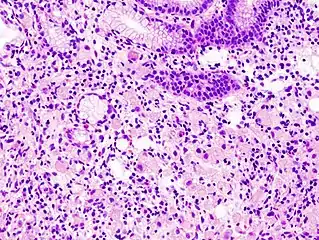

The name of the cell comes from its appearance; signet ring cells resemble signet rings. They contain a large amount of mucin, which pushes the nucleus to the cell periphery. The pool of mucin in a signet ring cell mimics the appearance of a finger hole and the nucleus mimics the appearance of the face of the ring in profile.

Gastric signet ring cell carcinoma. H&E stain.